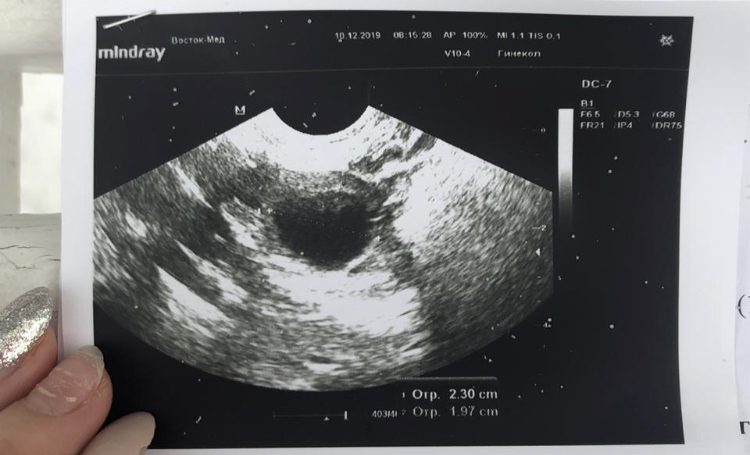

ФолликулометрияДевочки, привет!!! Сходила сегодня на узи (18 день цикла). Врач сказала, что овуляция была в правом яичнике! Но написала в заключении РЕТЕНЦИОННОЕ ОБРАЗОВАНИЕ размером 23мм x 19мм... То есть киста жёлтого тела. Пару циклов назад у меня была киста ЖТ, но она была почти 5 см!!!! А тут 23мм!!!

На УЗИ у кисты активный кровоток и зернистое включение. У Вас по картинке больше похоже на ЖТ, так как нет зерен. Но возможно именно по кровотока доктор определил что у Вас именно киста

Про кровоток она ничего не написала вообще) знаю только то, что она долго сомневалась киста или просто ЖТ..